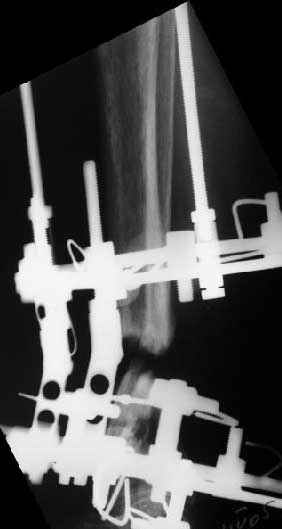

Аппарат - чтобы плавно исправить ось. В приложении - снимки на момент окончания коррекции в аппарате, фото с операции, и послеоперационная рентгенограмма.

Диаметр гвоздика 10,5 мм. Пришлось укорачивать до 23 см - уж очень миниатюрная дама, отверстия насверлил под 45 градусов, под 5 мм винты. По оси удалось сблизить до этого положения. Заперли гвоздь пока статически с планом через 2 месяца верхний винт убрать. Но это ей придется уже в Ташкенте сделать. Что скажете? Спасибо.

In attachment - x-rays at the end of alignment, the surgery, and result. The nail was cut to 23 cm. Four 45 degree holes were pre-drilled at the distal nail tip. The nail was locked statically

after some impaction. Dynamization is considered in 8 weeks. Any comments/critics?